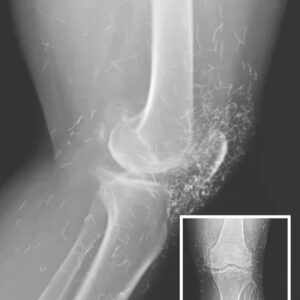

Doctors Stunned After Looking At This X-Ray Of Woman Suffering Joint Pain

A 65-year-old woman in South Korea went to the doctor for severe knee pain caused by osteoarthritis, but her X-ray revealed something shocking — hundreds of tiny…